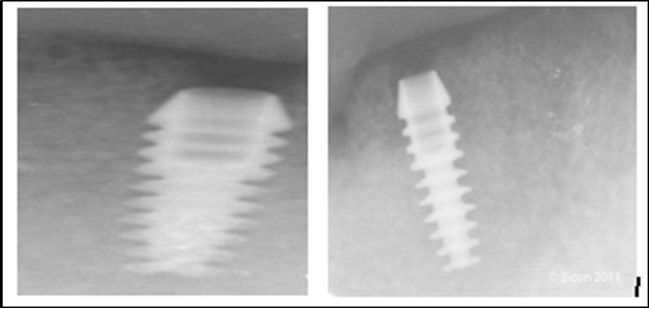

Post operatively after 3 months, osseointegration was evaluated clinically and radiographically (Figure 5a,b) and the implants were well prepared to receive the prosthesis. The second stage surgery was performed in which cover screws were removed and healing abutment were inserted into the implants (Figure 6). After a time period of two weeks, peri-implant soft tissue healing was examined, and existing denture was relined after relieving at the abutment site. Later, the healing abutment is removed using a 1.25 mm hex driver. Internal portion of the implant is irrigated and dried to make sure if it is free of debris and soft tissue. A periodontal probe was used to measure the gingival cuff height at the right and left canine site of implant location. Selected ball abutment were placed onto each implant using 1.25 mm hex driver and 30 Ncm torque wrench (Figure 7A).

Figure 5.a,b. Post-insertion radiographics in the mandibular area right,left,

a,b. Post-insertion radiographics  in the mandibular area right,left,